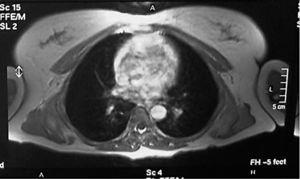

Mujer de 53 años, sin antecedentes de interés, remitida desde el servicio de cirugía general por tumoración en la espalda. La paciente refería dolor periescapular con los movimientos del hombro. En la exploración se observó una lesión abultada en la zona de la punta de la escápula izquierda que aumentaba de tamaño con la elevación y antepulsión del brazo (fig. 3). En la tomografía axial computerizada (TAC) se hallaron dos lesiones bilaterales entre pared torácica y escápulas, de mayor tamaño la izquierda, con apariencia similar al músculo. Lesión muy sugestiva de ED. Se realizó PAAF con resultado de extendido constituido por tejido adiposo. Se solicitó una RMN, que informó de ED bilateral (fig.4). El tratamiento sintomático no logró aliviar el dolor, que comenzó a ser bilateral. Finalmente se realizó una resección marginal de la tumoración sin complicaciones, obteniendo una pieza de aproximadamente 7 x 9 x 4 cm (fig. 5), analizada por anatomía patológica con el resultado de ED.

Figura 4. Elastofibroma dorsi bilateral.